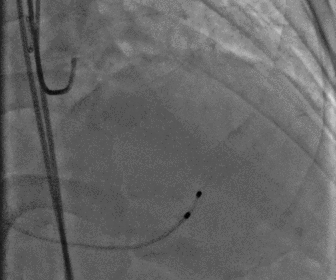

图片

左冠造影